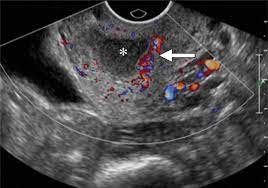

Pelvic Inflammatory Disease Diagnosis Ultrasound Imaging In Pelvic Inflammatory Disease